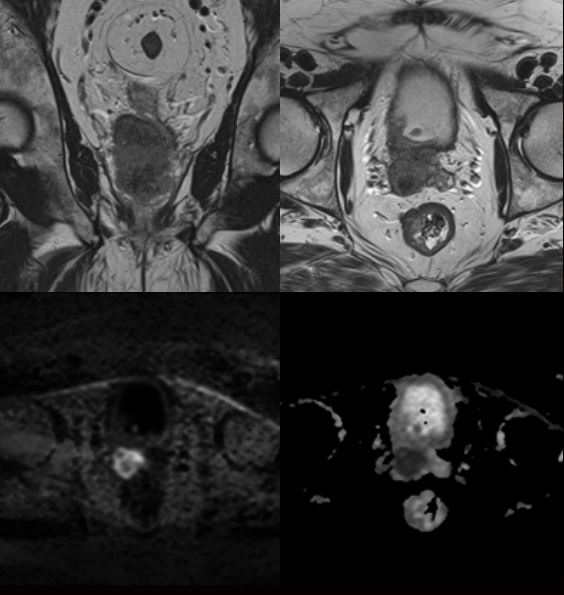

Чоловік 67 років, локальна стадія раку передміхурової залози.

Аксіальний та коронарний T2: товщина зрізів 3,5 мм/без зазору, поле огляду 200 мм.

Дифузія: базова послідовність SE EPI2D, товщина зрізу 3,5 мм/без зазору, поле огляду 220 × 220 мм, 3 значення b (100, 500, 1000), розраховане b = 2000.

3D T1 Динамічне сканування в аксіальній площині: 15 с на фазу, 1 попередня + 11 динамічних фаз, товщина зрізу 3,5 мм/без зазору, поле огляду 250 × 280 мм.